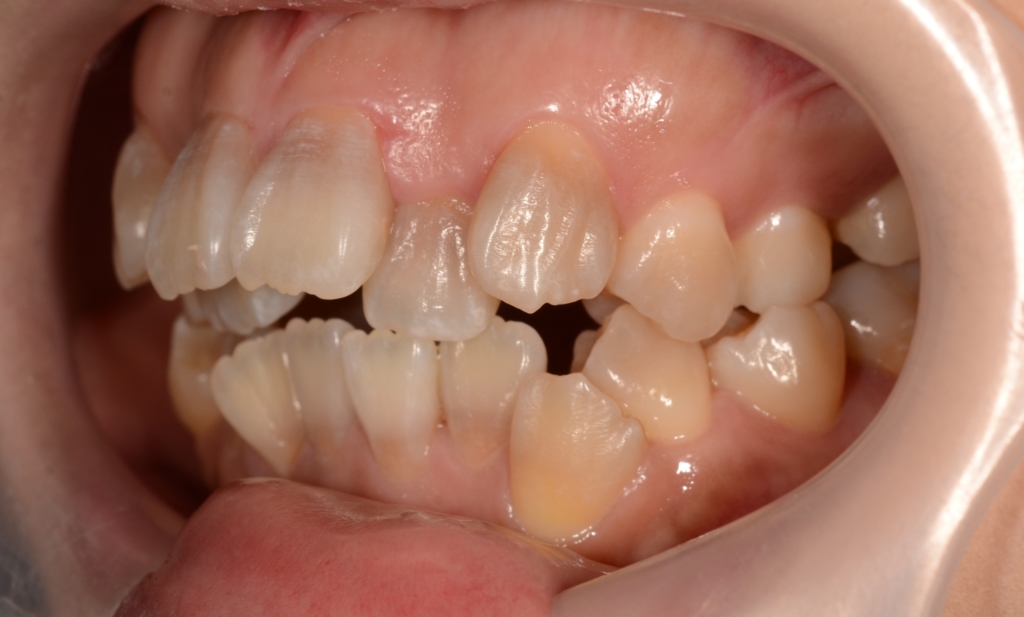

【Before】

#1.顎と歯の不調和による叢生(重度)

#2.上顎前突(出っ歯)

#3.開口

と診断しました。